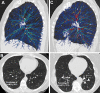

Background CT is the standard method used to assess bronchiectasis. A higher airway-to-artery diameter ratio (AAR) is typically used to identify enlarged bronchi and bronchiectasis; however, current imaging methods are limited in assessing the extent of this metric in CT scans. Purpose To determine the extent of AARs using an artificial intelligence-based chest CT and assess the association of AARs with exacerbations over time. Materials and Methods In a secondary analysis of ever-smokers from the prospective, observational, multicenter COPDGene study, AARs were quantified using an artificial intelligence tool. The percentage of airways with AAR greater than 1 (a measure of airway dilatation) in each participant on chest CT scans was determined. Pulmonary exacerbations were prospectively determined through biannual follow-up (from July 2009 to September 2021). Multivariable zero-inflated regression models were used to assess the association between the percentage of airways with AAR greater than 1 and the total number of pulmonary exacerbations over follow-up. Covariates included demographics, lung function, and conventional CT parameters. Results Among 4192 participants (median age, 59 years; IQR, 52-67 years; 1878 men [45%]), 1834 had chronic obstructive pulmonary disease (COPD). During a 10-year follow-up and in adjusted models, the percentage of airways with AARs greater than 1 (quartile 4 vs 1) was associated with a higher total number of exacerbations (risk ratio [RR], 1.08; 95% CI: 1.02, 1.15; P = .01). In participants meeting clinical and imaging criteria of bronchiectasis (ie, clinical manifestations with ≥3% of AARs >1) versus those who did not, the RR was 1.37 (95% CI: 1.31, 1.43; P < .001). Among participants with COPD, the corresponding RRs were 1.10 (95% CI: 1.02, 1.18; P = .02) and 1.32 (95% CI: 1.26, 1.39; P < .001), respectively. Conclusion In ever-smokers with chronic obstructive pulmonary disease, artificial intelligence-based CT measures of bronchiectasis were associated with more exacerbations over time. Clinical trial registration no. NCT00608764 © RSNA, 2022 Supplemental material is available for this article. See also the editorial by Schiebler and Seo in this issue.